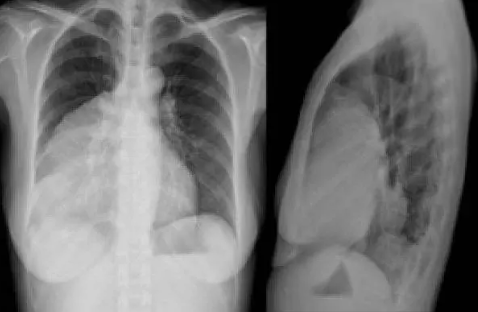

Yapılan incelemeler sonucunda, Xu'nun sağ akciğerinde yaklaşık 1 santimetrelik kitle fark eden doktorlar, bunun kötü huylu tümör olabileceği ihtimali üzerinde durdu.

Doktorlar, kanser olabileceği düşündükleri Xu'ya tam teşhis koyabilmek için akciğer dokusundan parça alarak testler yaptı. Yapılan testler sonucu, doktorların kötü huylu tümör sandığı kitlenin acı biber parçası olduğu anlaşıldı.

Biber parçasının, 2 yıl önce yemek yediği sırada boğazına kaçtığını ve şiddetli şekilde öksürdüğünü hatırlayan Xu'nun yaşadıkları Çin'deki sosyal medya platformlarında oldukça ilgi çekti.